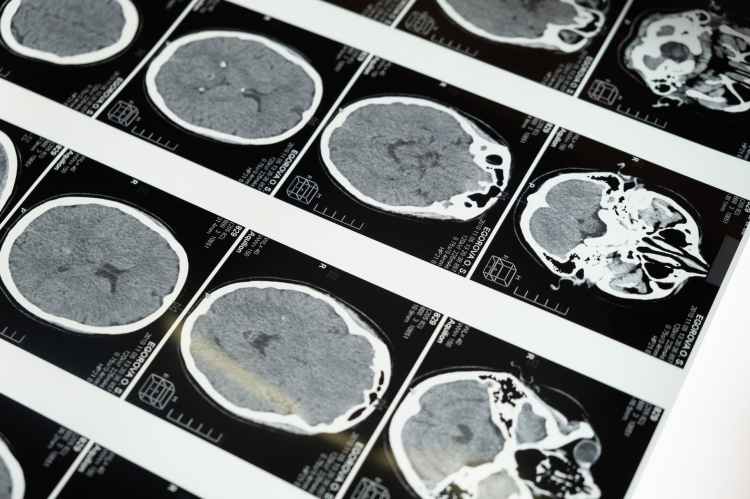

Além disso, oferecemos o exame de mapeamento cerebral com EEG digital, uma ferramenta avançada para a análise da atividade cerebral.

Diagnóstico e tratamento de uma ampla gama de condições que afetam o sistema nervoso, incluindo enxaqueca, epilepsia, demências (com destaque para Alzheimer e Vascular), Parkinson e outros distúrbios de movimento, AVC e distúrbios do sono. Utilizamos as mais avançadas técnicas e tecnologias para garantir um cuidado de excelência aos nossos pacientes.